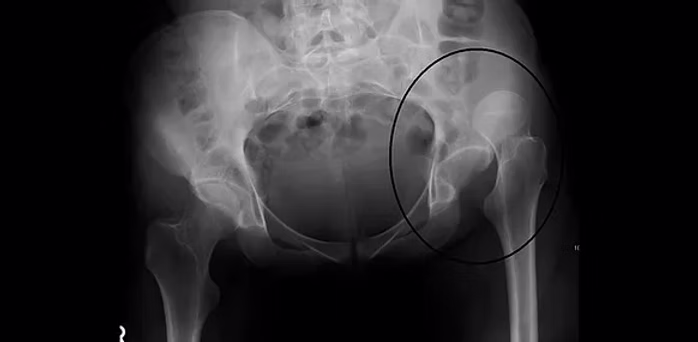

Luxația congenitală de șold este o malformație serioasă a articulației șoldului, care apare din cauza unei dezvoltări anormale între capul femural și cavitatea acetabulară. Netratată, această afecțiune poate afecta profund mersul, echilibrul și mobilitatea copilului.

Diagnosticul precoce este esențial și se bazează pe examinarea clinică și ecografia de șold efectuată ideal în prima lună de viață. Tratamentul variază în funcție de severitate și vârsta copilului – de la hamul Pavlik și imobilizări gipsate, până la intervenții chirurgicale și recuperare prin kinetoterapie specializată.